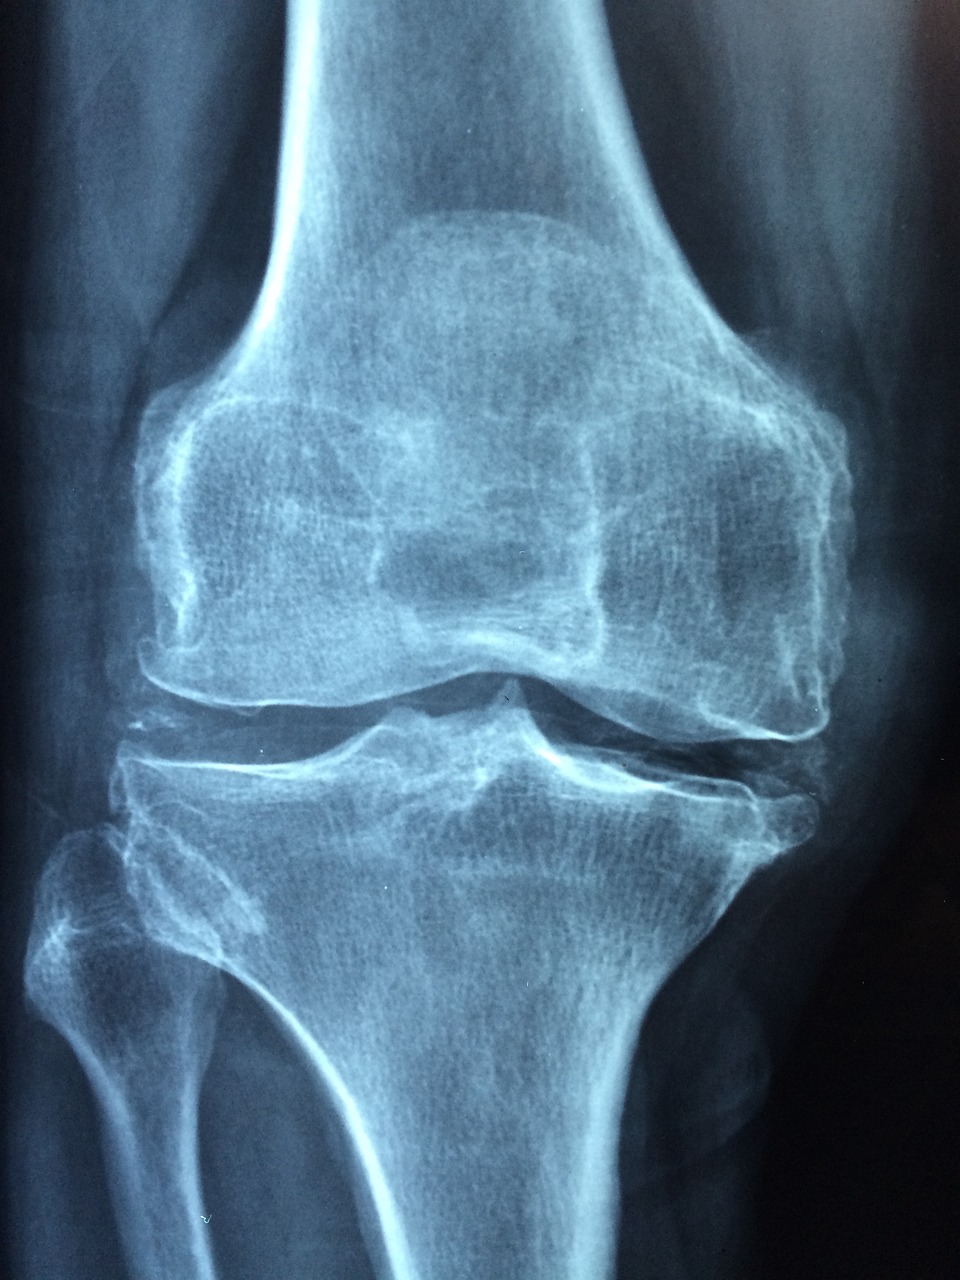

- ✔ 무릎 인공관절 수술비 지원

📌 무릎 인공관절 수술비 지원

- ✔ 한쪽 무릎: 최대 120만 원 지원

- ✔ 양쪽 무릎: 최대 240만 원 지원